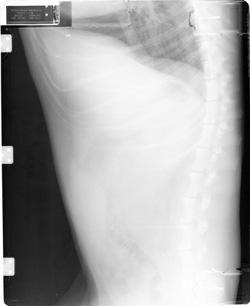

Upside Down Cassettes